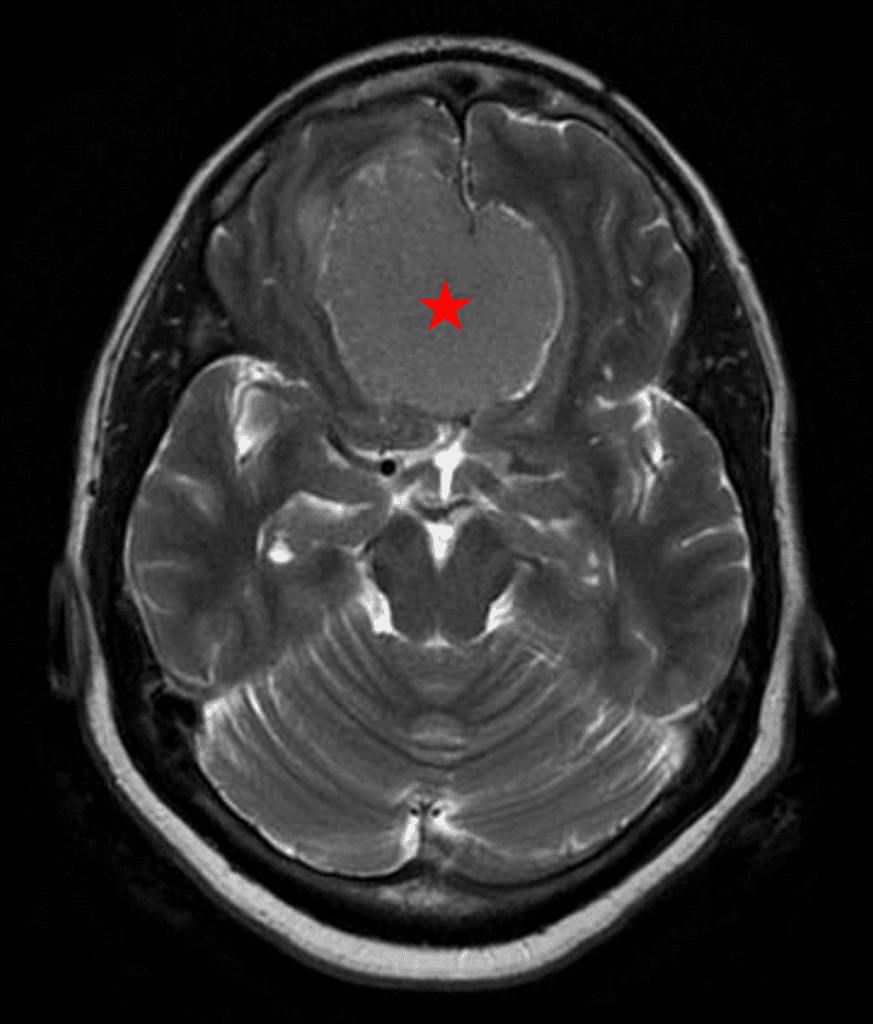

Figure 1b – Postoperative MRI demonstrating a complete resection without residual enhancement.

She was started on high-dose steroid and antiseizure prophylactic medicine. Surgical intervention was offered for mass effect, symptomatic relief, neurologic preservation, and histopathologic diagnosis. Dr. Gaudin performed a bifrontal craniotomy with complete resection of neoplasm through an interhemispheric and subfrontal approach. Postoperative imaging demonstrated a gross total resection without residual tumor and resolution of mass effect (Figure 1b and 2b). Intraoperative pathology was consistent with meningioma, WHO grade 1. She recovered very well, and was discharged home on postoperative day 3. On her follow-up outpatient visit, her preoperative symptoms had fully resolved, and her olfactory sense was maintained.